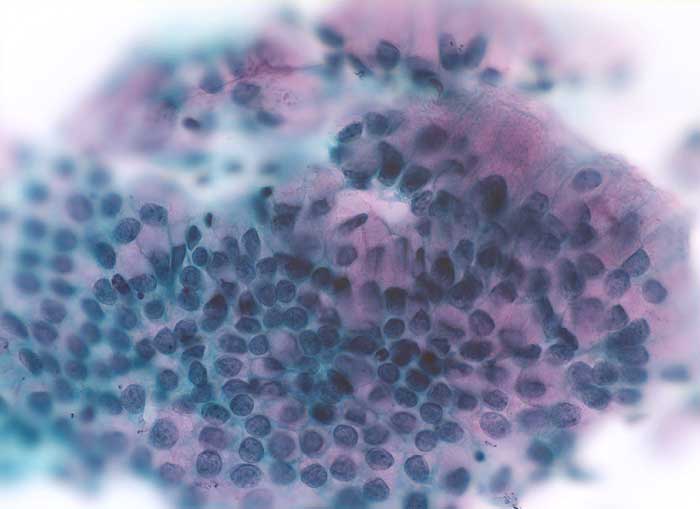

Atypische Zylinderepithelien bei Gestagentherapie

Endozervixzellen können unter Gestageneinfluss oder als Folge chronischer Reizzustände (Intrauterinpessar) Zellkernveränderungen wie beim endozervikalen Adenocarcinoma in situ ausbilden. Entsprechende klinische Angaben sind unabdingbar für die korrekte Interpretation dieser Veränderungen.